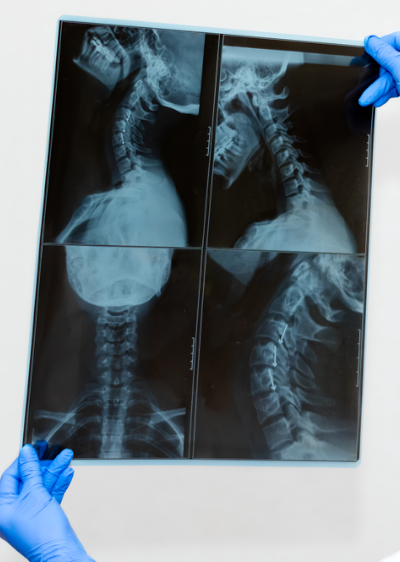

A Oncologia de Cabeça e Pescoço é a especialidade médica responsável por investigar, diagnosticar e tratar tumores que acometem a boca, garganta, laringe, faringe, glândulas salivares, tireoide e outras estruturas da região da cabeça e do pescoço. Entre as principais doenças estudadas e tratadas, estão:

Principais sintomas em cânceres de cabeça e pescoço:

A importância da Oncologia de Cabeça e Pescoço:

Os tumores de cabeça e pescoço exigem diagnóstico rápido e tratamento especializado para preservar funções essenciais, como fala, deglutição e respiração, além da estética facial. Consultas regulares e atenção a sintomas persistentes são fundamentais para a detecção precoce.